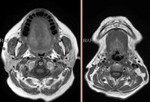

[画像診断]シェーグレン症候群の頚部MRI 【後期研修医と学ぶ】 2010-08-19